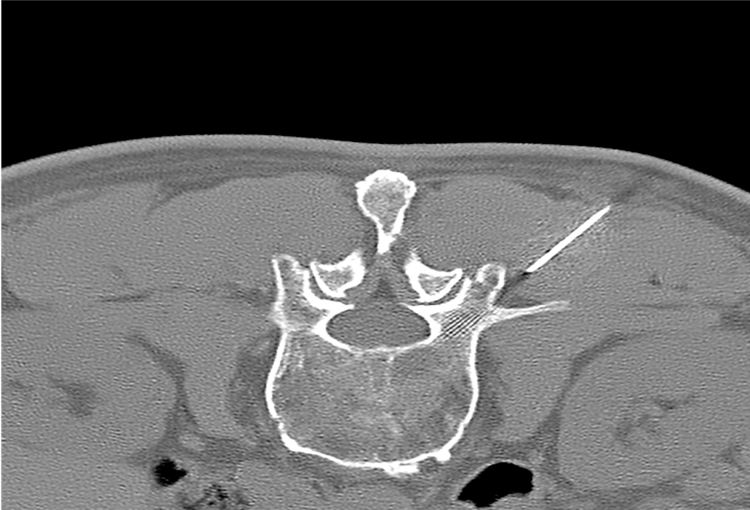

120 kV / 30 mAs / 1mm

Before FBP (Noise 150) VS After ClariCT.AI (Noise 49) 67% Denoising